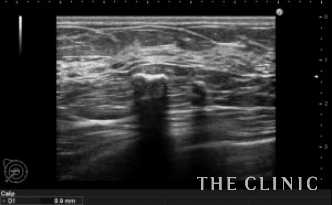

この方は大きなオイルシストと細かい石灰化が混在したしこりでした。

左がオイルシストです。 右は細かい石灰化です。

手で触れる多くのしこりはオイルシストで、細かい石灰化はほとんど触れません。